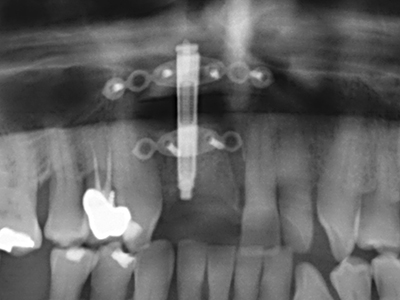

En la extracción de bloques óseos la piezocirugía también presenta ventajas adicionales: Además de la alta precisión en la osteotomía que ya se ha descrito antes, se ha comprobado que el uso de los delgados insertos de sierra resulta especialmente cuidadosas con el hueso. Frente a esto, sobre todo cuando se usan las fresas de Lindemann, cabe esperar pérdidas en la extracción significativamente más altas debido al mayor grosor de la parte frontal del cabezal (Lakshmiganthan, Gokulanathan et al. 2012). La separación basal que se necesita en particular en los injertos de bloque extraídos de forma retromolar se ve facilitada mediante sierras perpendiculares especialmente previstas a tal fin, lo que permite considerar que la cirugía piezoeléctrica es un procedimiento preciso y seguro para la obtención de bloques de hueso en el área retromolar (Happe 2007) (fig. 1-12).